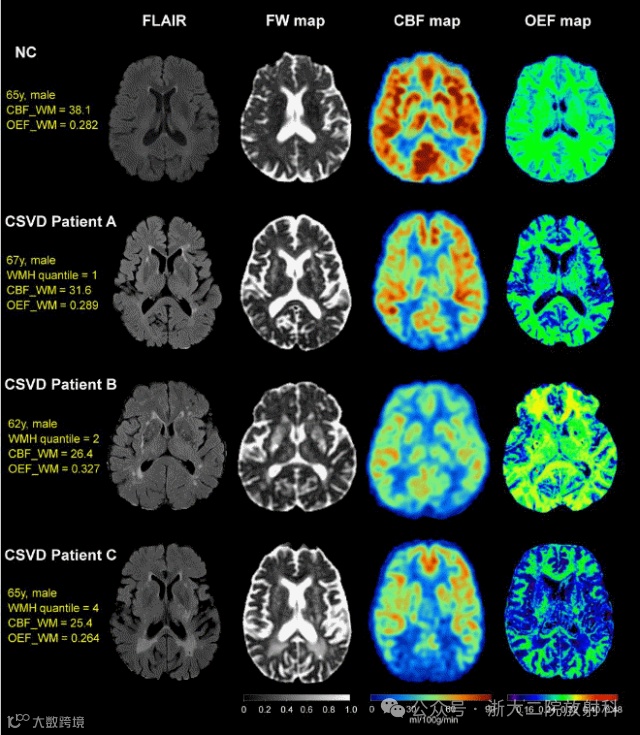

1. Zhang R, Lin M, Cho J, Yu X, Jiaerken Y, Wang S, .. Huang P. Oxygen extraction fraction in small vessel disease: relationship to disease burden and progression. Brain. 2025;148(6):1950-62.

脑氧代谢/脑血流改变对脑小血管病进展的贡献

慢性低灌注是脑小血管病(CSVD)的主要发病机制之一。既往研究表明,当脑组织灌注不足时,机体可通过上调氧摄取分数(OEF)进行代偿、缓解脑组织缺氧状态,然而该机制在CSVD中的作用仍有待明确。研究采用动脉自旋标记技术测量脑血流(CBF),并采用定量磁敏感图结合定量血氧水平依赖成像(QQ-OEF)技术测量OEF。采用脑白质高信号(WMH)体积、腔隙数量、脑白质自由水反映疾病负荷。研究发现脑小血管病患者脑白质区 “氧摄取分数” 随病灶负荷表现出 “先上升后下降” 的变化模式;在校正脑血流量后,基线氧摄取分数较高的患者疾病纵向进展相对较慢。该成果表明,脑氧代谢在脑小血管病发生发展中起着重要作用,基于磁共振测量的氧摄取分数有望成为脑小血管病临床研究的重要工具。